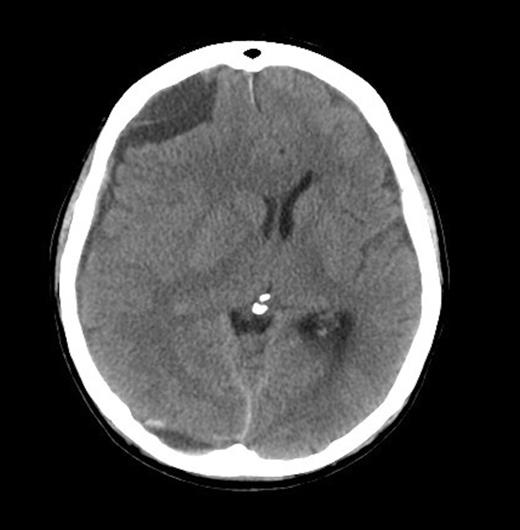

A 62-year old male presented to the emergency department of our institution with epistaxis, anaemia (Hb: 48g/L) and thrombocytopenia (platelets: 52x109/L). Past history included a diagnosis of metastatic prostate adenocarcinoma 7 years earlier. He denied headaches and there were no neurological deficits other than mild cognitive impairment. He was noted to be coagulopathic with an INR of 1.5, despite platelet, fresh frozen plasma and red blood cell transfusion, his coagulopathy ultimately worsened. His level of consciousness deteriorated and a CT Brain was performed identifying acute on chronic SDH (Figure 1 & 2).